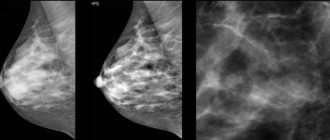

Маммография: Чего ожидать и как минимизировать боль В 2011 году более 500 000 женщин